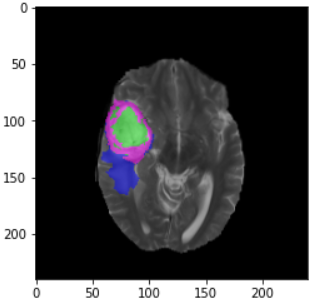

plt.imshow(nda[n, :, :]) # n为要读取的切片

plt.imshow(nda1[n, :, :]) # n为要读取的切片